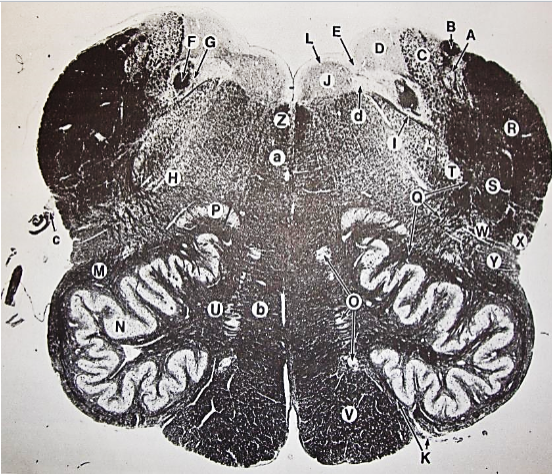

A

Fasciculus gracilis

B

gracile nucleus

C

fasciculus cuneatus

D

cuneate nucleus

E

spinal trigeminal tract

F+G collectively

spinal trigeminal nucleus

H

accessory nucleus

I

pyramidal decussation

J

rubrospinal tract

K

posterior spinocerebellar tract

L

anterior spinocerebellar tract

M

lateral spinothalamic tract

N

anterior spinothalamic tract

O

lateral vestibulospinal tract

P

medial longitudinal fasciculus

Q

tectospinal tract